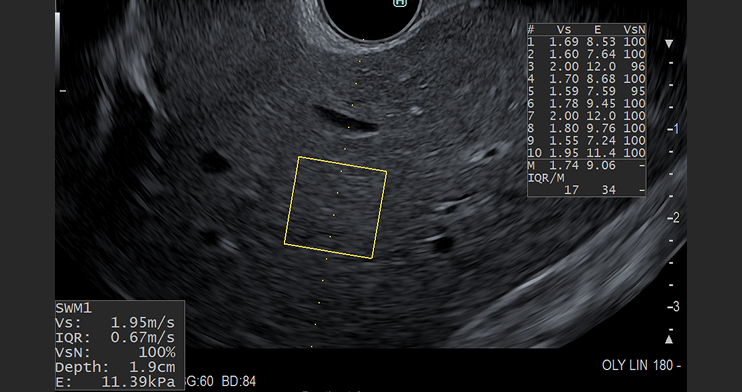

Shear Wave Measurement (SWM)

SWM is used to assess tissue stiffness, such as liver fibrosis. A “push-pulse” generates shear waves, which propagate through the tissue, perpendicular to the ultrasound beam. SWM then provides an assessment of tissue stiffness by calculating the propagation velocity of the shear waves (Vs). Hitachi’s SWM technology provides an additional reliability indicator (VsN), as an objective evaluation of the Vs measurement. The reliability indicator gives physicians confidence that they are basing clinical decisions on stable and accurate measurement result.10